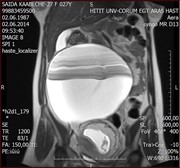

A rare case of paratubal cystadenoma during pregnancy

Umit Gorkem and others

Journal of Surgical Case Reports, Volume 2016, Issue 1, January 2016, rjv169, https://doi.org/10.1093/jscr/rjv169